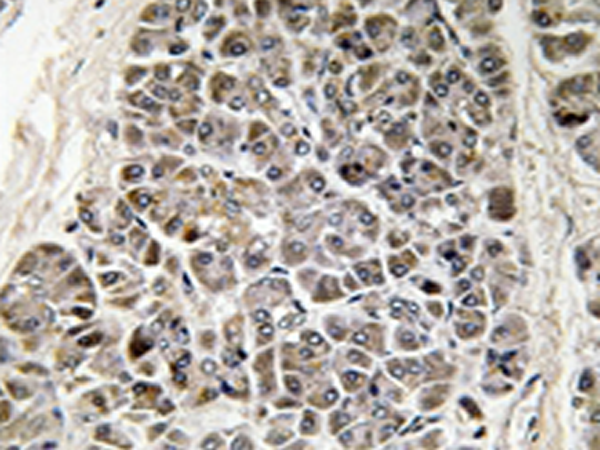

IHC positive control: |

Human pancreas tissue |

IHC Recommend dilution: |

50-100 |